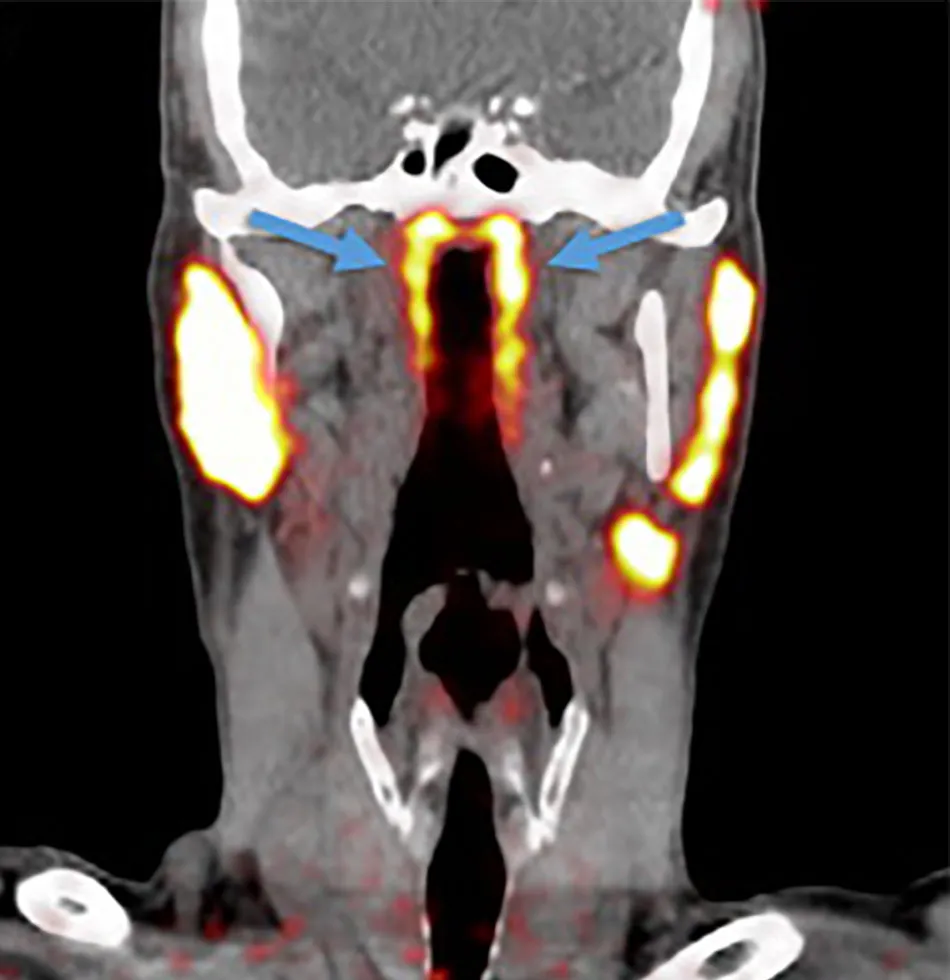

ନେଦରଲ୍ୟାଣ୍ଡର ବୈଜ୍ଞାନିକମାନେ ଏକ ନୂଆ କ୍ୟାନ୍ସର ସ୍କେନ୍ ଯାଞ୍ଚ କରୁଥିବା ବେଳେ ଗଳାରେ ଏକ ନୂଆ ଅଙ୍ଗ ବିଷୟରେ ଜାଣିବାକୁ ପାଇଥିଲେ। ଗବେଷଣାରୁ ଜଣାପଡ଼ିଲା ଯେ ମଣିଷ ଗଳାର ଉପରିଭାଗରେ ଗ୍ରନ୍ଥୀଗୁଡ଼ିକର ଏକ ଗ୍ରୁପ ରହିଛି। ବୈଜ୍ଞାନିକମାନେ ଏହି ଗ୍ରନ୍ଥୀର ନାମ Tubarial salivary glands ରଖିବା ସହିତ ଏହା ନାକର ଲୁବ୍ରିକେସନ୍ରେ ସାହାଯ୍ୟ କରିଥାଏ ବୋଲି ବୈଜ୍ଞାନିକମାନେ କହିଛନ୍ତି।

Radiotherapy and Oncology ଜର୍ନାଲରେ ପ୍ରକାଶିତ ଏକ ରିପୋର୍ଟ ଅନୁସାରେ, ରେଡିଏସନ୍ ଚିକିତ୍ସା ସମୟରେ ଯଦି ଏହି ଗ୍ରନ୍ଥୀଗୁଡ଼ିକ ଉପରେ କୌଣସି ପ୍ରଭାବ ନ ପଡ଼େ ତେବେ ଏହା ମଣିଷ ପାଇଁ ଉପକାରୀ ହେବ। ନେଦରଲ୍ୟାଣ୍ଡର ଏମ୍ସଟର୍ଡସର କ୍ୟାନ୍ସର ଇନଷ୍ଟିଚ୍ୟୁଟ୍ର ବୈଜ୍ଞାନିକ ପ୍ରୋଷ୍ଟେଟ୍ କ୍ୟାନ୍ସର ଯାଞ୍ଚ ପାଇଁ ପ୍ରସ୍ତୁତ କରାଯାଇଥିବା PSMA PET-CT ନାମକ ସ୍କାନ୍ର ପରୀକ୍ଷଣ କରୁଥିବା ସମୟରେ ରେଡିୟେକ୍ଟିଭଭ ଟ୍ରେସରକୁ ରୋଗୀର ସରିର ଇଞ୍ଜେକ୍ଟ କରାଯାଇଥିଲା ରେଡିୟେକ୍ଟିଭଭ ଟ୍ରେସର ପାଇଁ ମଣିଷ ଶରୀରେ ଥିବା ନୂଆ ଅଙ୍ଗ ବିଷୟରେ ଜଣାପଡ଼ିଥିଲା।/odishatv-khabar/media/post_attachments/aajtak/images/photo_gallery/202010/new-organ_020212.jpg)

ଗଳାର ଉପରିଭାଗରେ ଥିବା ଏହି ଗ୍ରନ୍ଥୀଗୁଡ଼ିକର ଲମ୍ବ ୧.୫ ଇଞ୍ଚ ରହିଛି। ଏହି ନୂତନ ଗ୍ରନ୍ଥୀଗୁଡ଼ିକ salivary glands ଭଳି। ୧୦୦ ଲୋକଙ୍କ ଉପରେ ହୋଇଥିବା ରିସର୍ଚ ସମୟରେ ପ୍ରାୟ ୧୦୦ ଲୋକଙ୍କଠାରେ ହିଁ ଏହି ଗ୍ରନ୍ଥୀ ଥିବା ଜଣାପଡ଼ିଥିଲା।